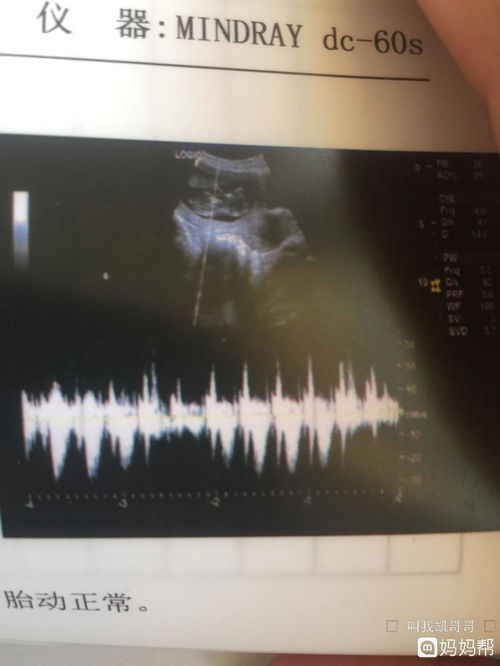

nub点是指NT检查图片上的胎儿特征点和尾椎的角度,一般在进行超声检查的时候,会出现nt中的nub点,很多人会在进行检查之后,进行寻找nub点,并来借此判断肚子里孩子的性别。

这个结节一般在孕12之后开始发育,但是孕妈做nt的。